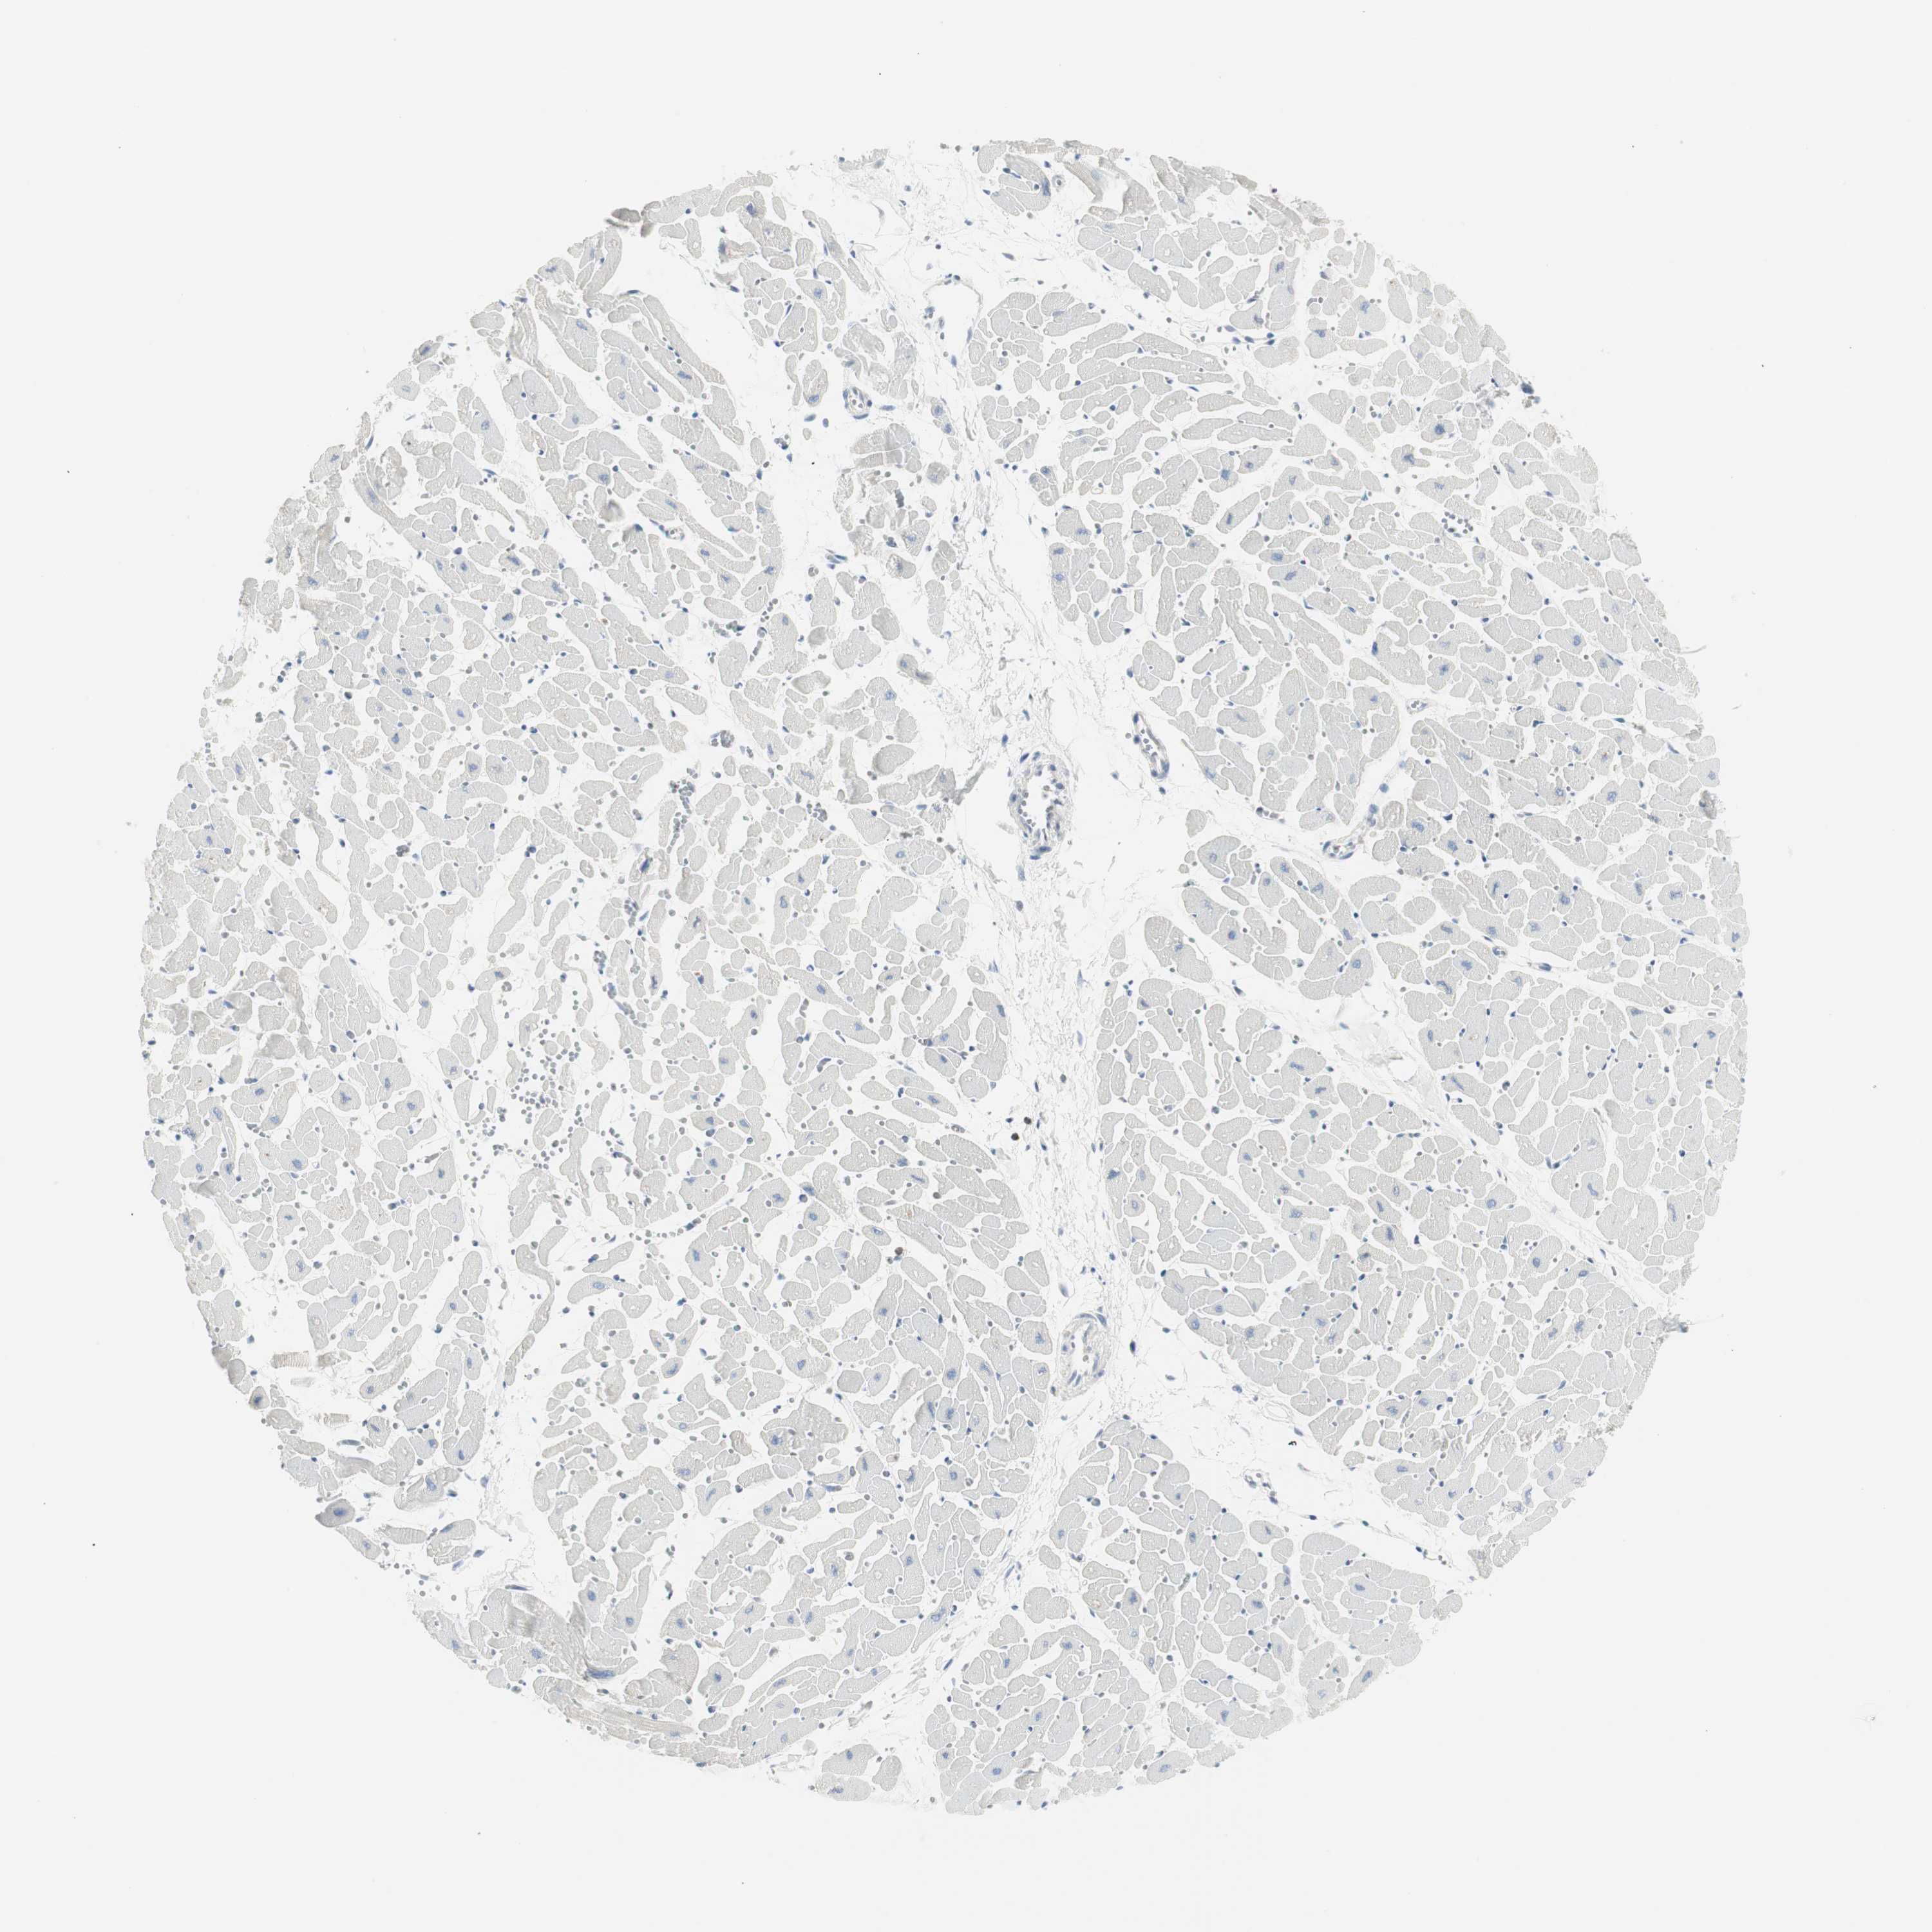

HEART MUSCLE - Antibody stainingi

Antibody staining in the annotated cell types in the current human tissue is reported as not detected, low, medium, or high, based on conventional immunohistochemistry profiling in selected tissues. This score is based on the combination of the staining intensity and fraction of stained cells.

Each image is clickable and will lead to virtual microscopy that enables deeper exploration of all samples and also displays staining intensity scores, fraction scores and subcellular localization as well as patient and tissue information for each sample.

Antibody HPA046833Antibody CAB004545

Cardiomyocytes MediumNot detected